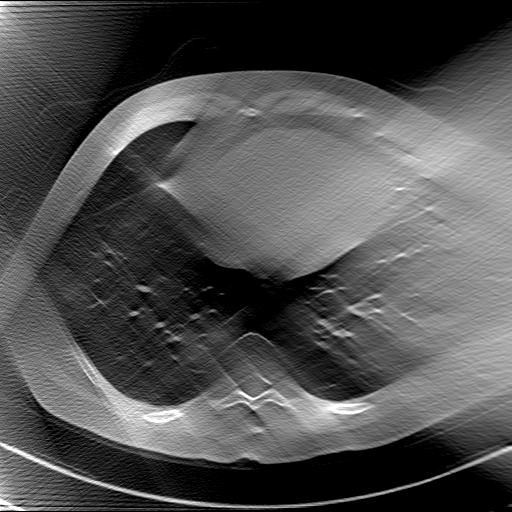

GT

FBP

HQS-CG

DuDoNet

Meta

Meta_re

EPNet

Qualitative Results Comparison. We also visualize the reconstruction results of these methods on AAPM-test and COVID-test datasets. As in the first three rows of Fig. 4, the reconstructed images from ours and retrained MetaInvNet show the best visualization quality on AAPM-test set across different angle numbers. Besides, our results show sharper details with the additional utilization of in the projection domain. When testing the reconstructed image on the COVID-test set, our result also gives sharper details but with more artifacts since the data distribution is very different. Although HQS-CG has achieved better quantitative results on the COVID-test dataset, the reconstructed image of their model in the fourth row is even smoother than FBP.